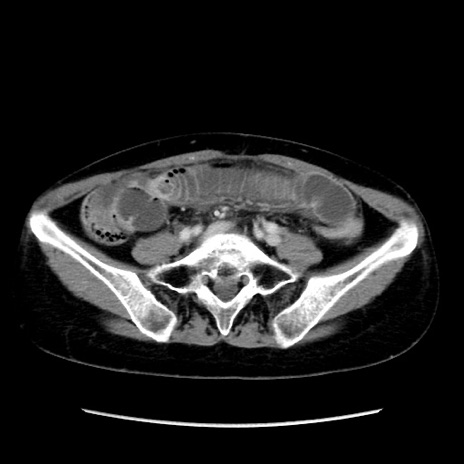

冠状断像

矢状断像